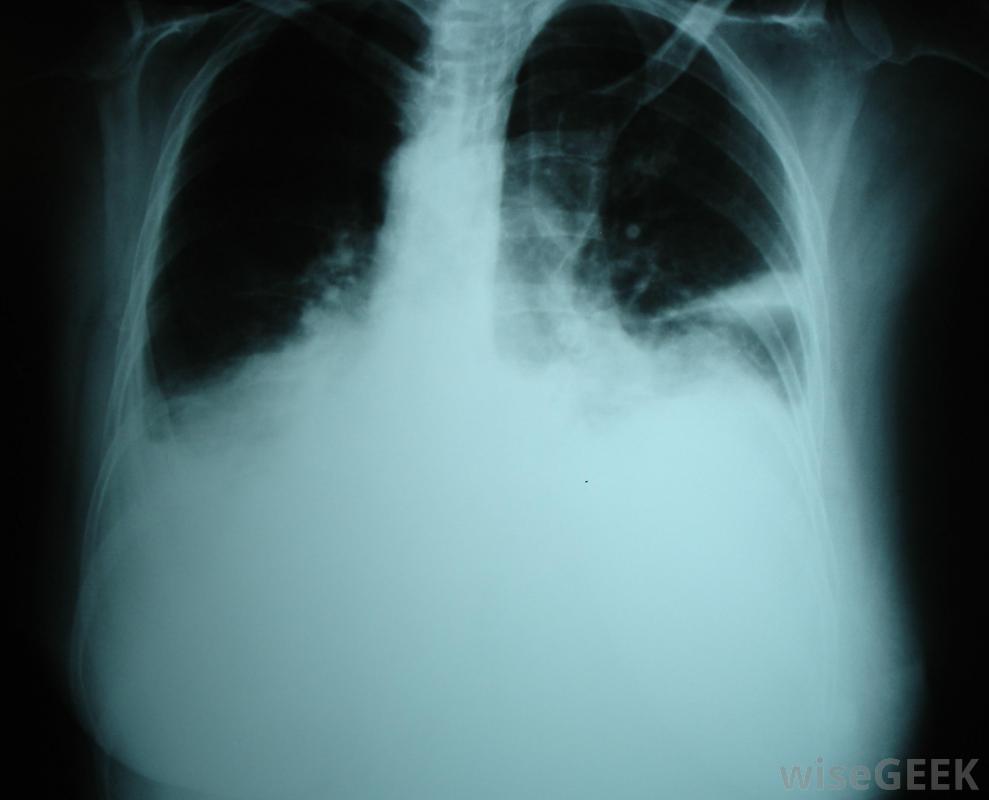

渗出性胸腔积液是一种富含蛋白质的液体在肺部周围的腔中积聚,这是由肺部及其周围组织的局部损伤引起的。这种损伤导致细胞开始渗出液体,有时非常迅速。这与渗出性胸腔积液形成对比,系统性过程使血管更具渗透性并增加压力,导致水样液体开始漏入胸腔。检测可以确定是哪种积液,也可以缩小病因。

癌症、创伤,感染是胸腔积液的可能原因。癌症、外伤和感染都是渗出性胸腔积液的可能原因。在所有这些病例中,局部的细胞损伤会迫使细胞泄漏蛋白质和其他物质。虽然胸膜腔通常有一些液体来润滑肺部,但当太多液体积聚时,很难呼吸。胸部的一侧或两侧可能受累,患者通常会出现呼吸困难、奇怪的呼吸音和问题像紫绀一样,由于氧合不足,四肢开始发蓝。

可以通过X光来诊断胸腔积液医生可以插入针头或引流管来迅速缓解积液液体的样本可以被带到实验室进行分析,以了解体内发生的情况。如果是渗出性胸腔积液,那么这些样本中的蛋白质水平会很高。蛋白质和其他物质的平衡也可以为胸腔积液的病因提供线索,就像恶性胸腔积液一样渗出性胸腔积液的症状可能包括呼吸困难渗出性胸腔积液的治疗首先要排出多余的液体,这样病人就可以更容易地呼吸了。一旦病人病情稳定,就可以开始对病因进行评估和治疗。治疗方案可以包括抗生素等治疗感染,以及治疗肺部及周围的癌性肿瘤。在诊断过程中,医生可能会召集专家来咨询,因为在诊断过程中会收集到更多关于积液的信息。